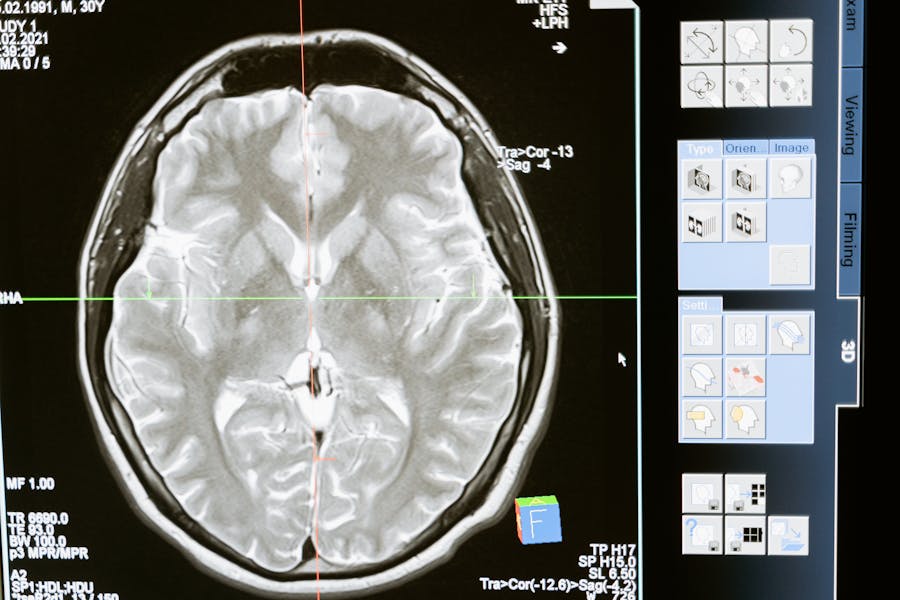

Dependiendo de tus respuestas y de los hallazgos del examen físico, tu médico puede sugerir pruebas adicionales, como una resonancia magnética (MRI) o una tomografía computarizada (CT), para descartar otras causas y llegar al corazón de tu problema.